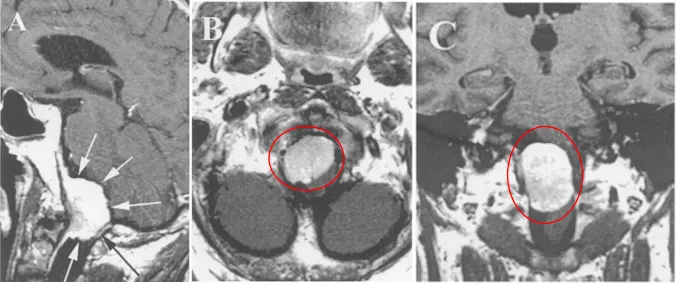

(A–C)术前MRI

术前:了解病变的前后、左右的比邻关系,了解病变的特性

值得注意的是,为了更好的手术,术前检查的影像必须展示以下信息:病灶硬膜附着的确切部位与范围;肿瘤整体大小及侵袭范围;脑干与颈髓的移位方向及程度;椎动脉管径及其被包绕情况;肿瘤血供来源及丰富程度;枕骨大孔及邻近骨性结构的具体形态;是否存在解剖变异;脑干信号改变。